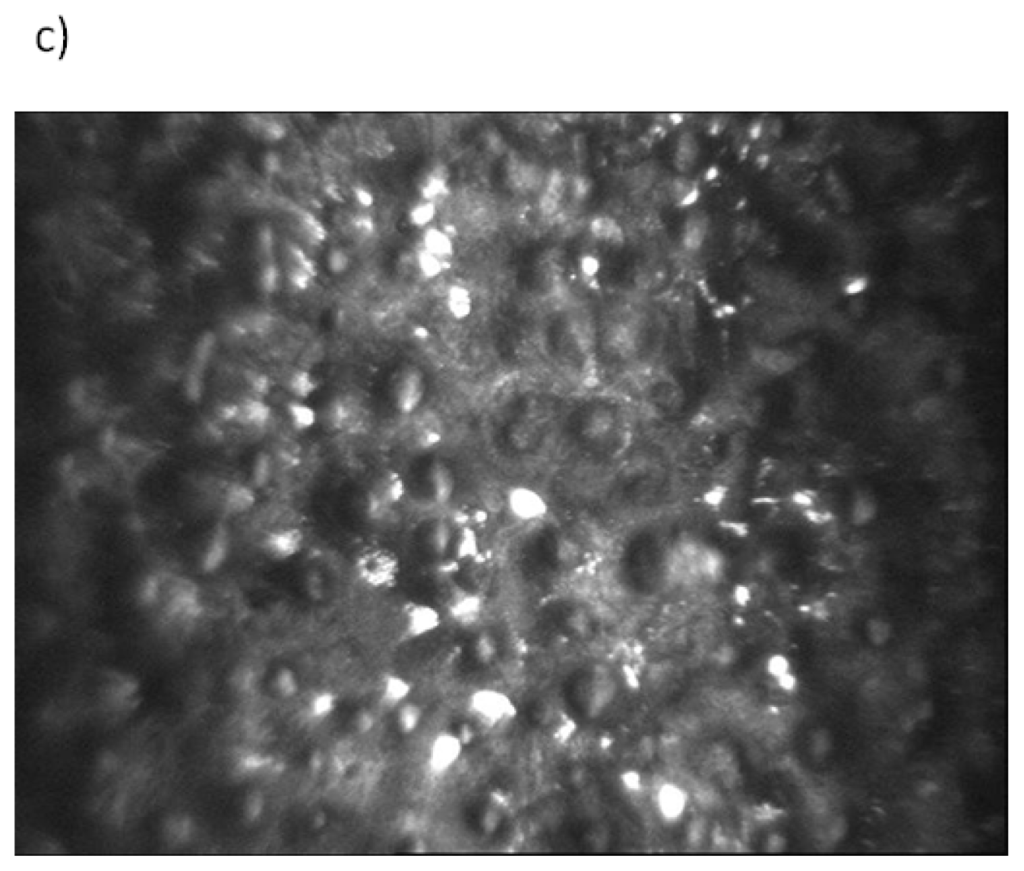

Figure 3.

Endothelium and Descemet’s membrane from normal cornea (a) and cornea in Fuchs endothelial corneal dystrophy (FECD) (b) showing structural changes, including guttae formation, modification of hexagonal endothelial cell mosaic and Descemet’s membrane thickening in FECD. Representative confocal microscopy image of endothelial guttae in advanced stage of FECD obtained from a patient of the Department of Ophthalmology, Medical University of Warsaw, Warsaw, Poland, is shown in part (c).